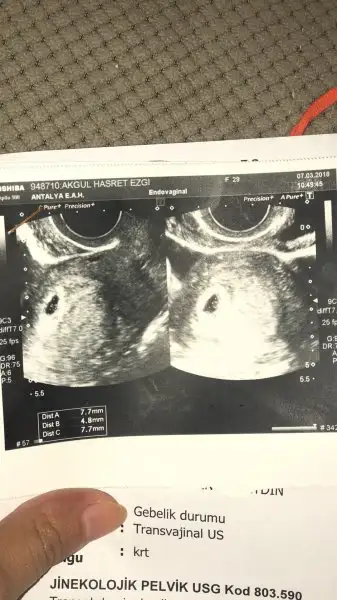

15.haftadayım henüz cinsiyet öğrenemedim bide buna yorum yapabilir misiniz vajinal ultrason görüntüsü

Vajinal ise ve yanlış anlamadıysam bu teoriye göre erkek gibi yine tecrübeli arkadaşlar daha iyi bilir